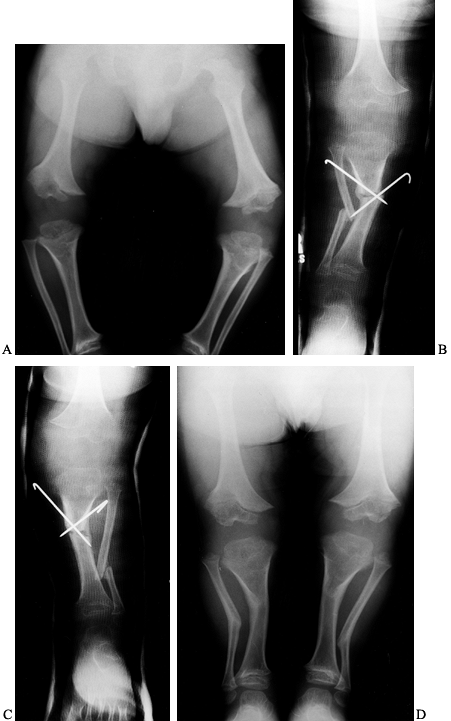

Figure 169.11. A:

Standing preoperative radiographs of a 6-year-old Caucasian boy with achondroplasia genu varum demonstrating the typical epiphyseal and metaphyseal changes, as well as overgrowth of the fibulae. B: Postoperative radiograph after proximal tibial and fibular diaphyseal valgus derotation osteotomies of the right leg shows that internal fixation was achieved with percutaneous smooth Steinmann pins. C: Postoperative radiograph of the left lower leg. D: Standing radiographs 6 months postoperatively demonstrates satisfactory healing and excellent correction of the genu varum deformities. |